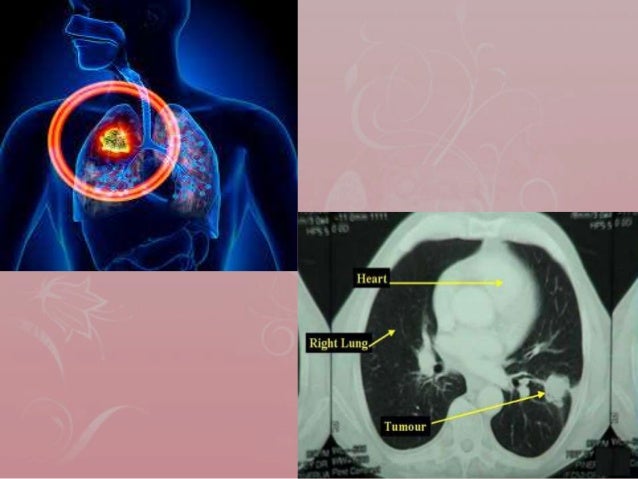

PPT - “No Air” Management Of Lung Cancer PowerPoint Presentation - ID

PPT - “No Air” Management of Lung Cancer PowerPoint Presentation - ID www.slideserve.com

lung metastatic survival